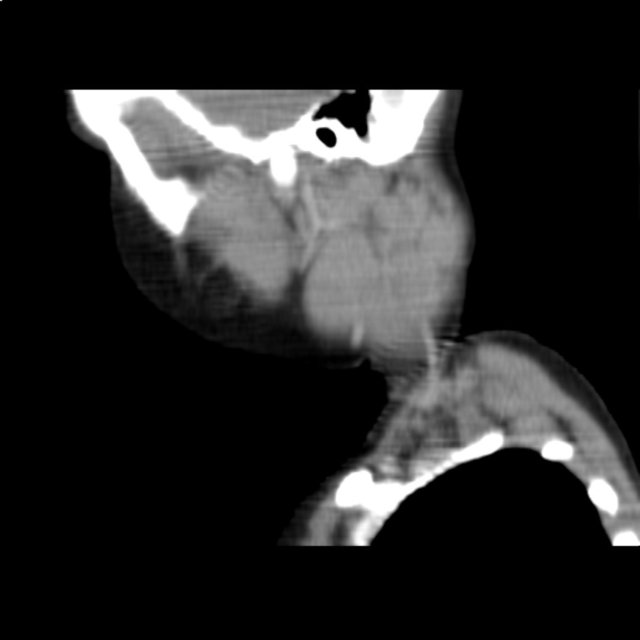

Computertomographie des Halses bei hochmalignem Non-Hodgkin-Lymphom der Halslymphknoten (rekonstruierter Sagittalschnitt) © wikipedia.de/Christaras A, CC BY 2.5